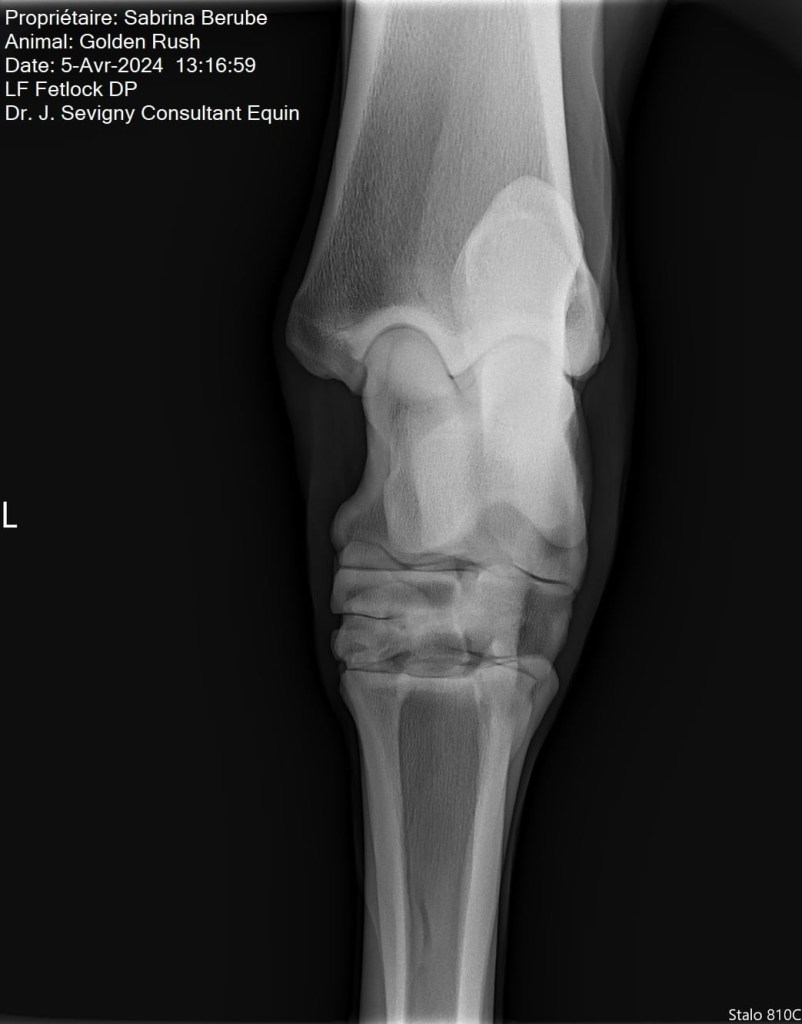

Par la suite, lors de la visite de ma vétérinaire, on a pris des radios de ses jarrets suite à son examen. Il n’a pas répondu tant que ça aux tests de flexion, mais tout de même il y a avait un petit quelque chose. Sur les radios, on a pu constater une présence d’arthrose modérée, ce qui venait expliquer le tout. Rien de surprenant vu son âge et sa discipline par contre, ce qui m’a rassurée un peu, mais je voulais traiter le problème. Je vous laisse les images pour vous donner une idée, je ne suis pas une experte en lecture de radio mais en gros, les espaces dans l’articulation sont sensés faire toute la longueur de l’articulation, mais dans le cas de mon cheval (surtout son jarret droit), l’arthrose est présente et fusionne les parties de l’articulation ensemble.